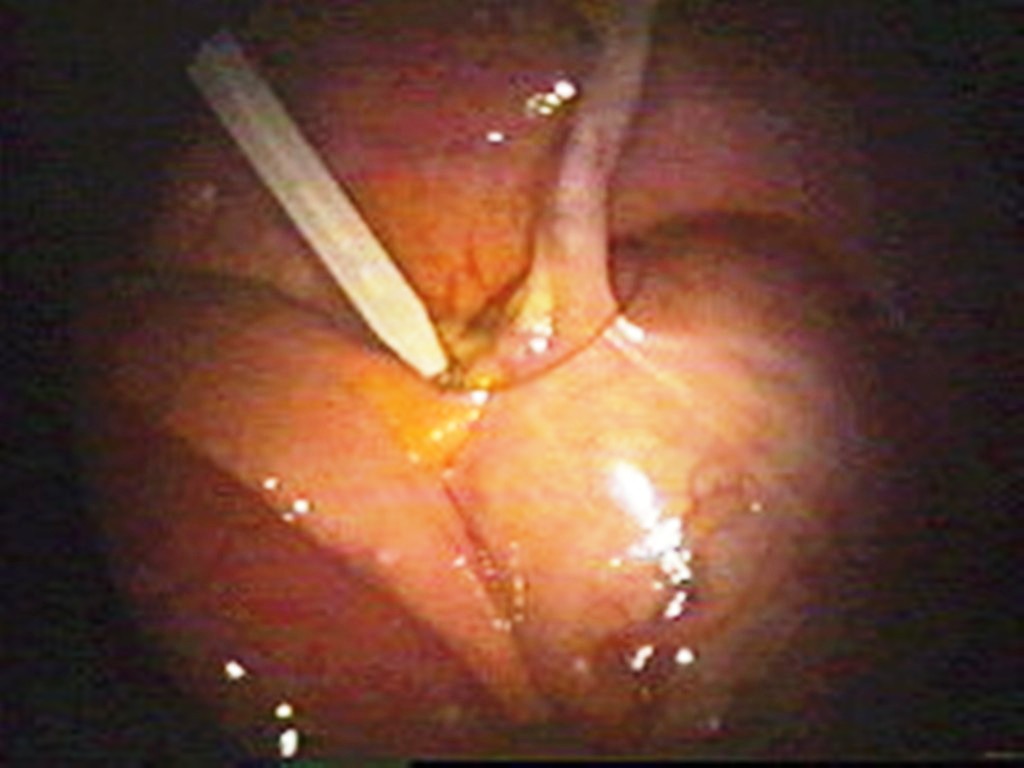

At Remedy Hospital we offer surgery for all conditions of appendix like appendicitis, appendicular malignancy, and mucocele of appendix. We offer surgery by latest technique (Laparoscopic Appendectomy) as well as time tasted conventional technique (Open Appendectomy).